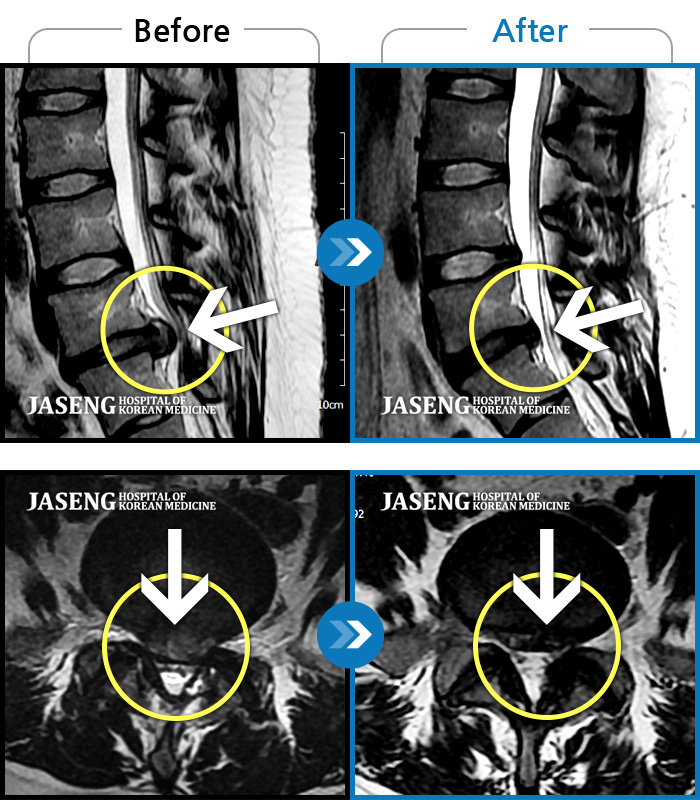

허리디스크로 다른병원에서 시술후 결과가 좋지않아

걷지도, 앉지도 못하는 저를 지극정성 6개월넘게 치료해주신덕에 현제는 걷는것도 뛰는운동도 하며 잘지내고 있습니다

디스크가 완치가 없다보니 가끔 무리가될때면 간혹 원장님 치료가 필요할때가 있더라고요.